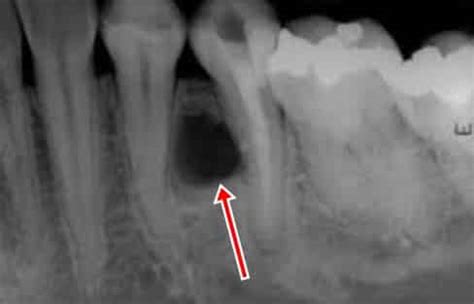

Radiografía periapical mostrando lesión radiolúcida unilocular bien definida entre las raíces de los dientes adyacentes. Fuente: ResearchGate